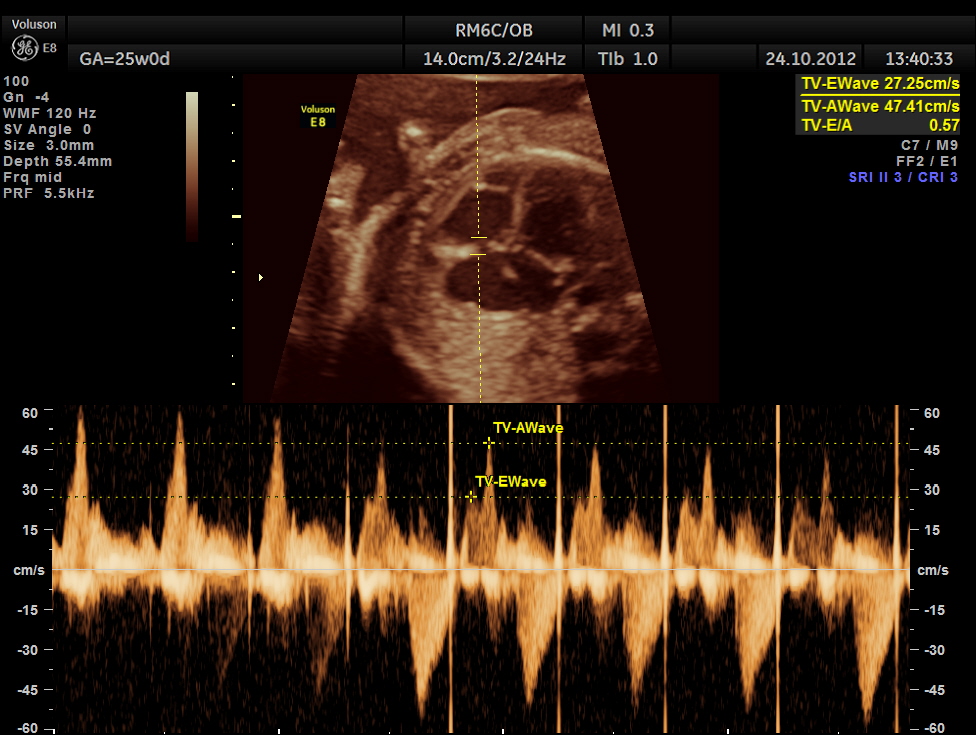

the following are spectral doppler flow across the 4 valves